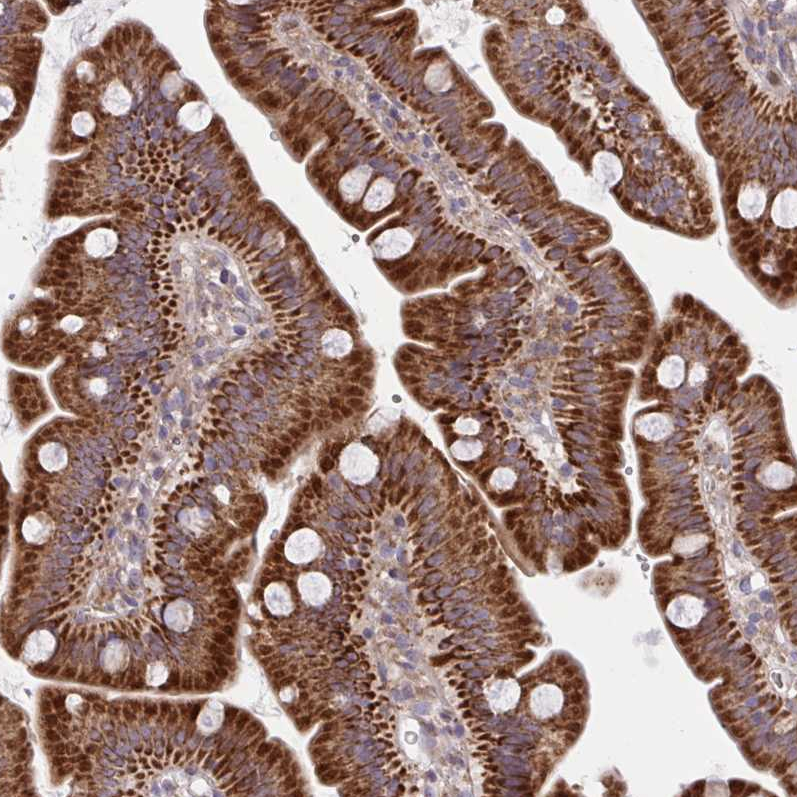

Immunohistochemical staining of human stomach shows strong cytoplasmic positivity in glandular cells.